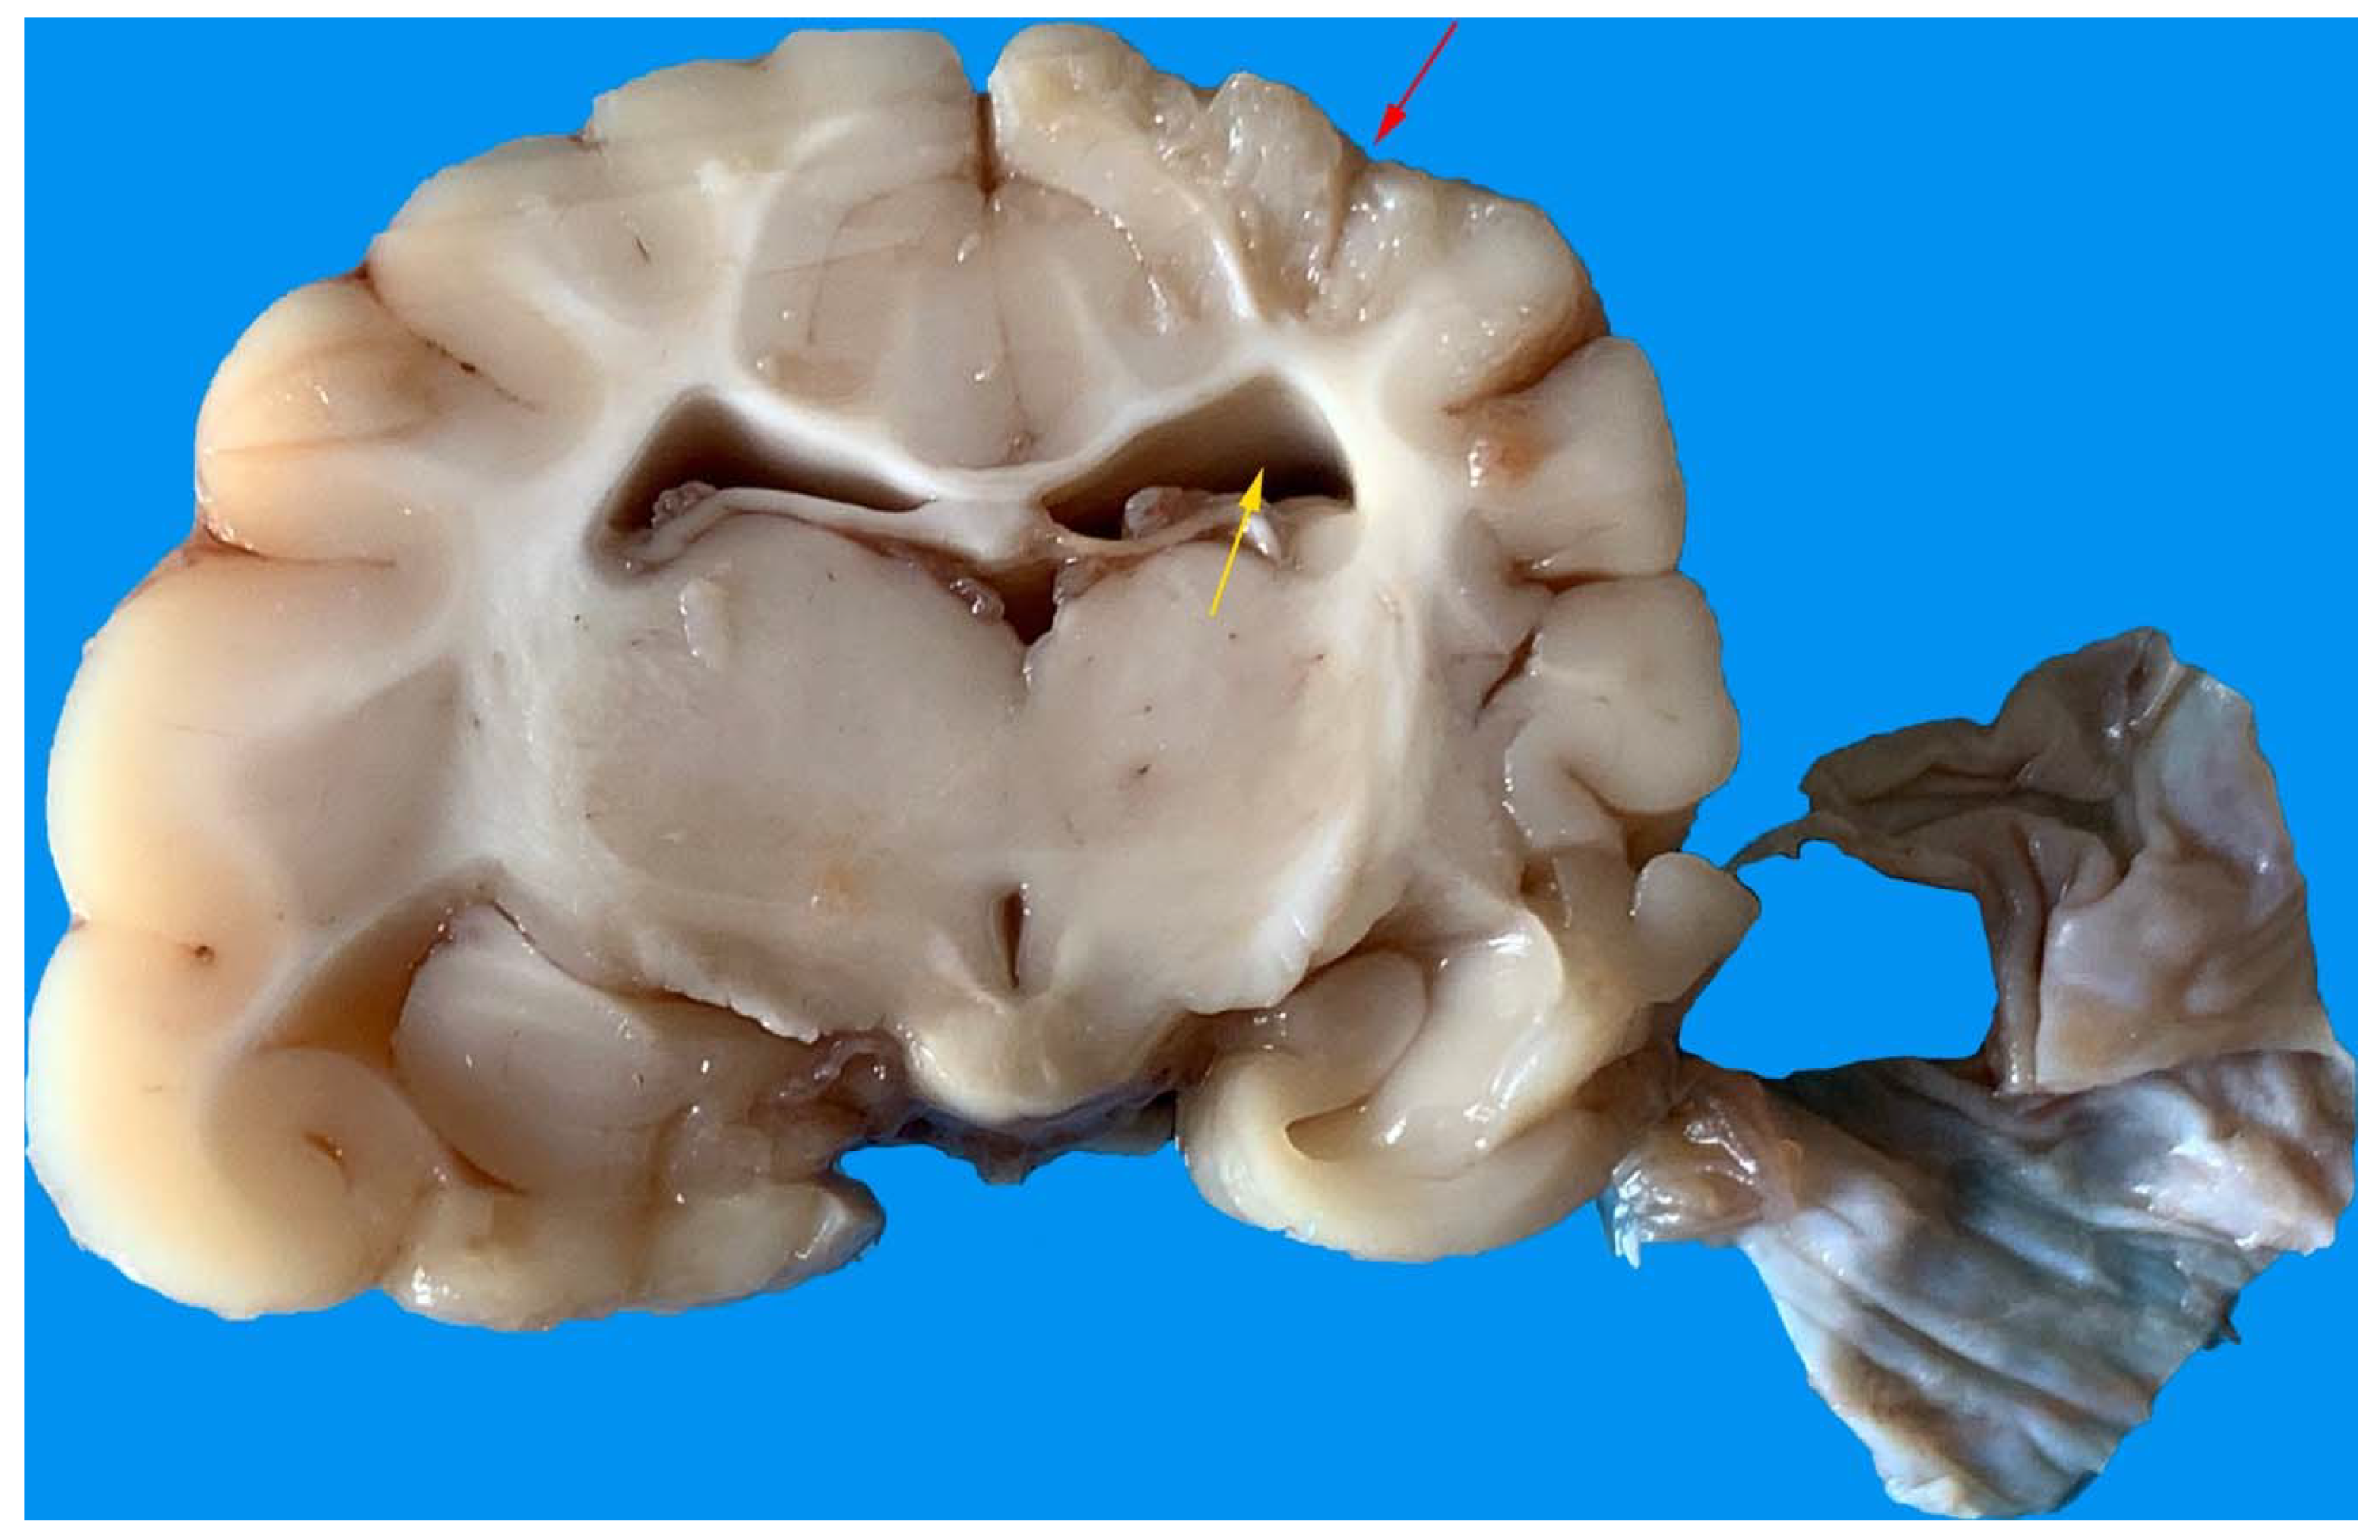

3.5. Gross Anatomy and Histological Findings